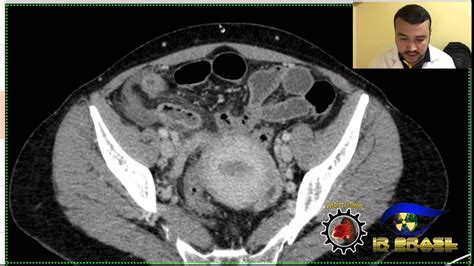

apendicite tomografia computadorizada

A apendicite consiste na inflamação e infecção do apêndice. Geralmente, o bloqueio dentro do apêndice faz com que o órgão se inflame e fique infectado. O exame mais utilizado para o diagnóstico de apendicite é a tomografia computadorizada (tc) com contraste intravenoso. Para detectar apendicite, o médico (geralmente um clínico geral) escuta o histórico de sintomas do paciente e parte para um exame físico,. Weba apendicite é causada por uma obstrução do órgão, que pode acontecer na presença de parasitas, tumores, infecções bacterianas ou virais e, até.